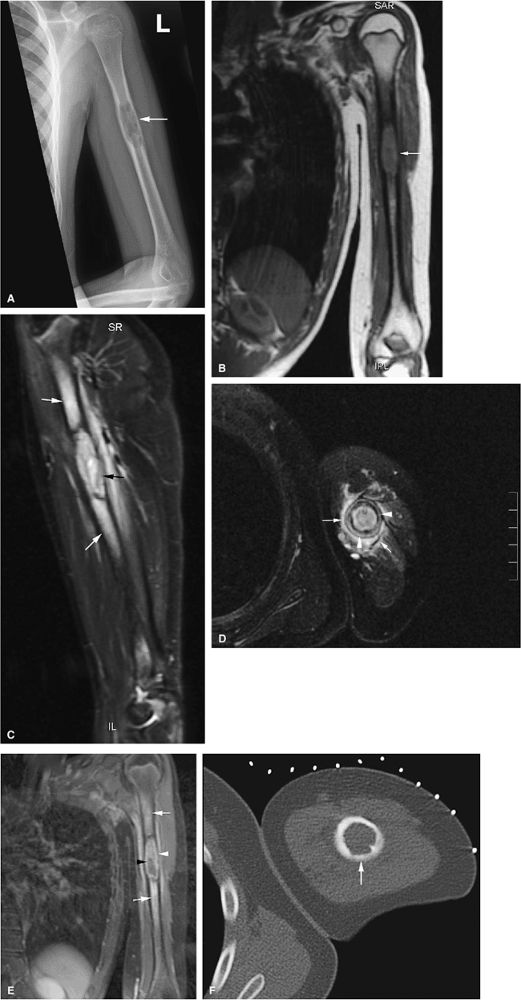

metaphysis or extend to the physeal plate (Fig. 13.39). There may also be localized bone expansion, indicated by a low-signal-intensity sclerotic peripheral border. Eosinophilic granuloma may be associated with perilesional or peritumoral edema. In the vertebral body, eosinophilic granuloma may present as a vertebra plana with diffuse infiltration of the vertebral body (Figs. 13.40, 13.41, and 13.42). Typical characteristics on T1- and T2-weighted images, however, are nonspecific for the diagnosis of eosinophilic granuloma. Age, location and morphology of signal intensity changes, is important in determining a differential diagnosis.

FIGURE 13.38 ● Langerhans cell histiocytosis of the humeral diaphyses. (A) Anteroposterior radiograph shows an expansile lytic lesion in the humeral diaphysis (arrow). (B) Coronal T1-weighted image shows low-signal-intensity histiocytic infiltration (arrow). (C) The lesion is hyperintense on a coronal STIR image (black arrow). Surrounding edema is hyperintense (white arrows). (D) Cortical thickening (white arrowheads) and surrounding edema (white arrows) are noted on an axial fat-suppressed T2-weighted image. (E) On a coronal fat-suppressed T1-weighted image following the intravenous administration of gadolinium, there is enhancement of the diaphyseal lesion (white arrowhead) with a central nonenhancing area (black arrowhead). Enhancing edema surrounds the lesion (white arrows). (F) Axial CT image obtained during percutaneous biopsy shows the expansile lytic lesion (arrow).